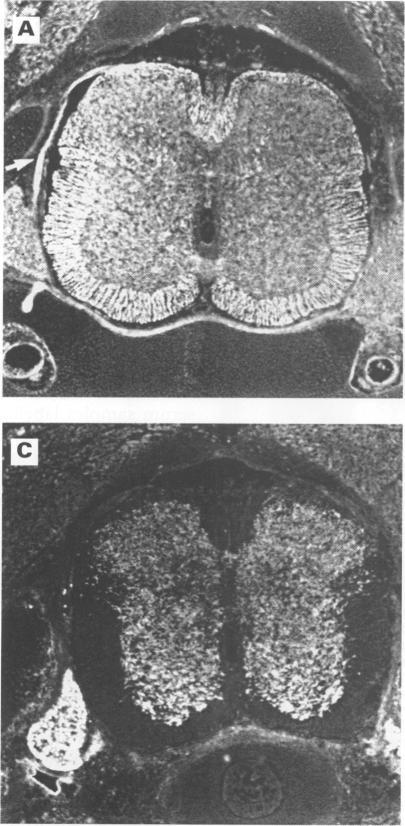

Of 45 patients with PNS whose serum was probed on paraformaldehyde fixed rat brain sections, 11 patients were identified whose serum samples recognised a cytoplasmic antigen in a subpopulation of glial cells in the white matter of adult rat brainstem, cerebellum, and spinal cord that were double labelled with a monoclonal antibody specific for oligodendrocytes. All serum samples reacted with a 66 kDa protein of newborn rat brain on western blot analysis. These antibodies were designated as anti-CV2 antibodies. Only one of the 11 patients had one of the well characterised autoantibodies (anti-Hu). Five patients had cerebellar degeneration, three had limbic encephalitis, two had encephalomyelitis, and one had Lambert-Eaton myasthenic syndrome. The tumours were small cell lung cancer or undifferentiated mediastinal cancer in seven patients, uterine sarcoma in two, and malignant thymoma in two. Among 1061 control serum samples, only two patients had anti-CV2 antibodies. One had small cell lung cancer and the other malignant thymoma.

在45例PNS患者中,用其血清检测经多聚甲醛固定的大鼠脑切片,发现11例患者的血清样本能识别成年大鼠脑干、小脑和脊髓白质中胶质细胞亚群的一种胞质抗原,这些胶质细胞用少突胶质细胞特异性单克隆抗体进行了双重标记。所有血清样本在蛋白质印迹分析中均与新生大鼠脑的一种66 kDa蛋白发生反应。这些抗体被命名为抗CV2抗体。11例患者中只有1例具有一种已明确的自身抗体(抗Hu)。5例患者有小脑变性,3例有边缘叶脑炎,2例有脑脊髓炎,1例有兰伯特-伊顿肌无力综合征。肿瘤在7例患者中为小细胞肺癌或未分化纵隔癌,2例为子宫肉瘤,2例为恶性胸腺瘤。在1061份对照血清样本中,只有2例患者有抗CV2抗体。1例患有小细胞肺癌,另1例患有恶性胸腺瘤。